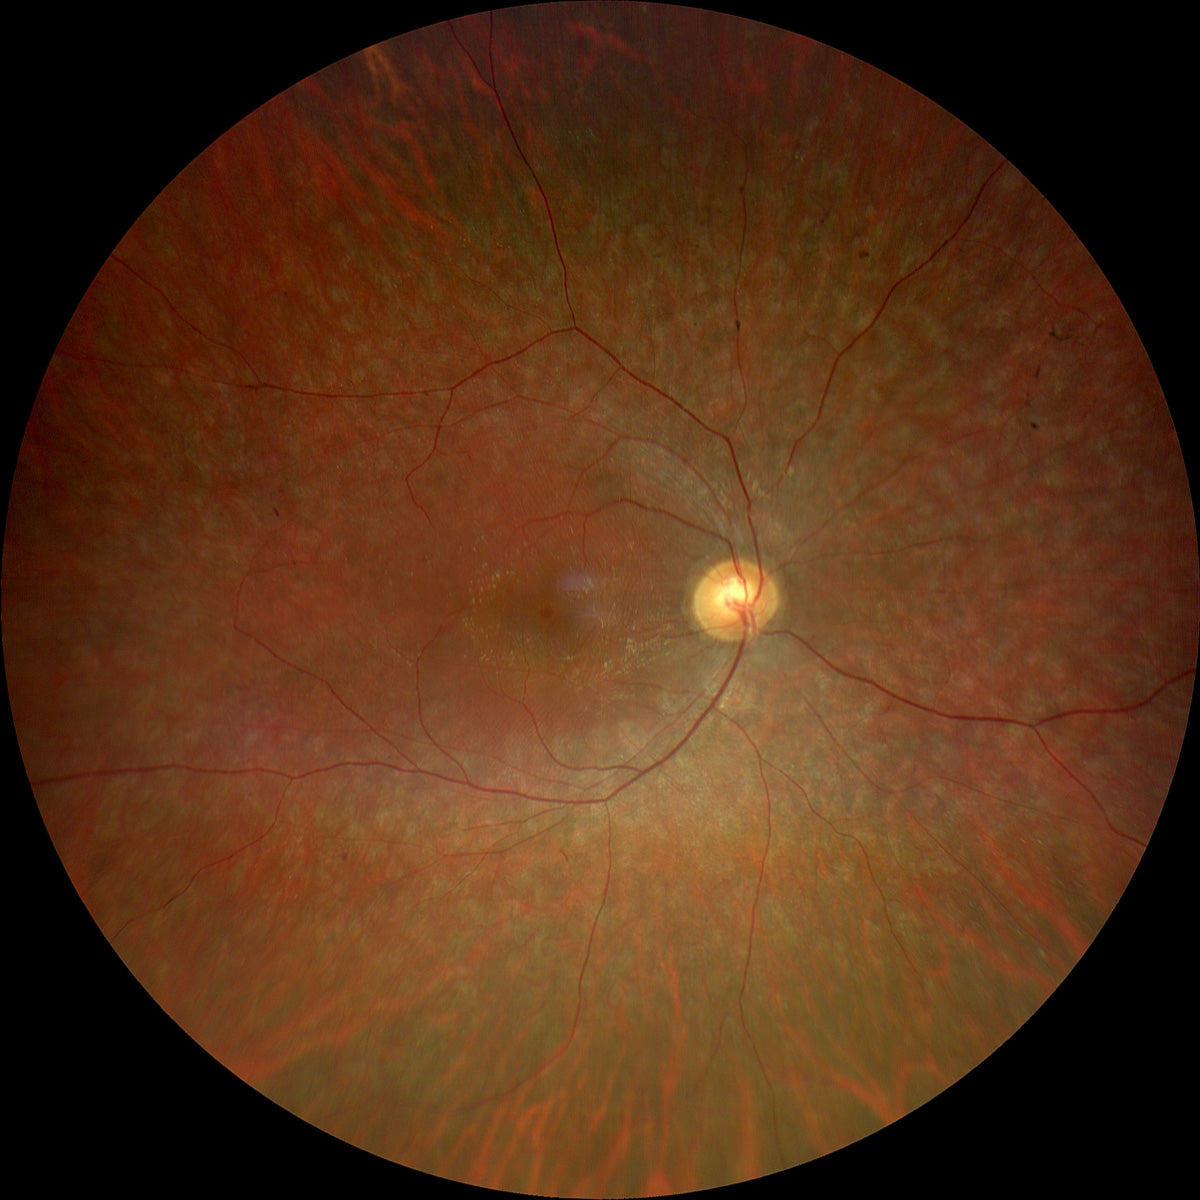

La Retinite Pigmentosa (spesso chiamata anche Retinite Pigmentosa) è una malattia oculare degenerativa che coinvolge la retina e, in particolare, i fotorecettori responsabili della visione notturna e periferica. Si tratta di una patologia genetica e progressiva, che nel tempo può determinare un restringimento del campo visivo, alterazioni della percezione luminosa e una significativa difficoltà nella visione in condizioni di scarsa illuminazione.

La malattia colpisce prima i bastoncelli (responsabili della visione periferica e crepuscolare) e, in fasi successive, può coinvolgere anche i coni, compromettendo anche la visione centrale e dei colori.

• difficoltà a vedere al buio o in ambienti poco illuminati (nictalopia);

• visione tubolare, dovuta al restringimento progressivo del campo visivo;

• difficoltà a percepire ostacoli laterali;

• in stadi avanzati, riduzione della visione centrale.